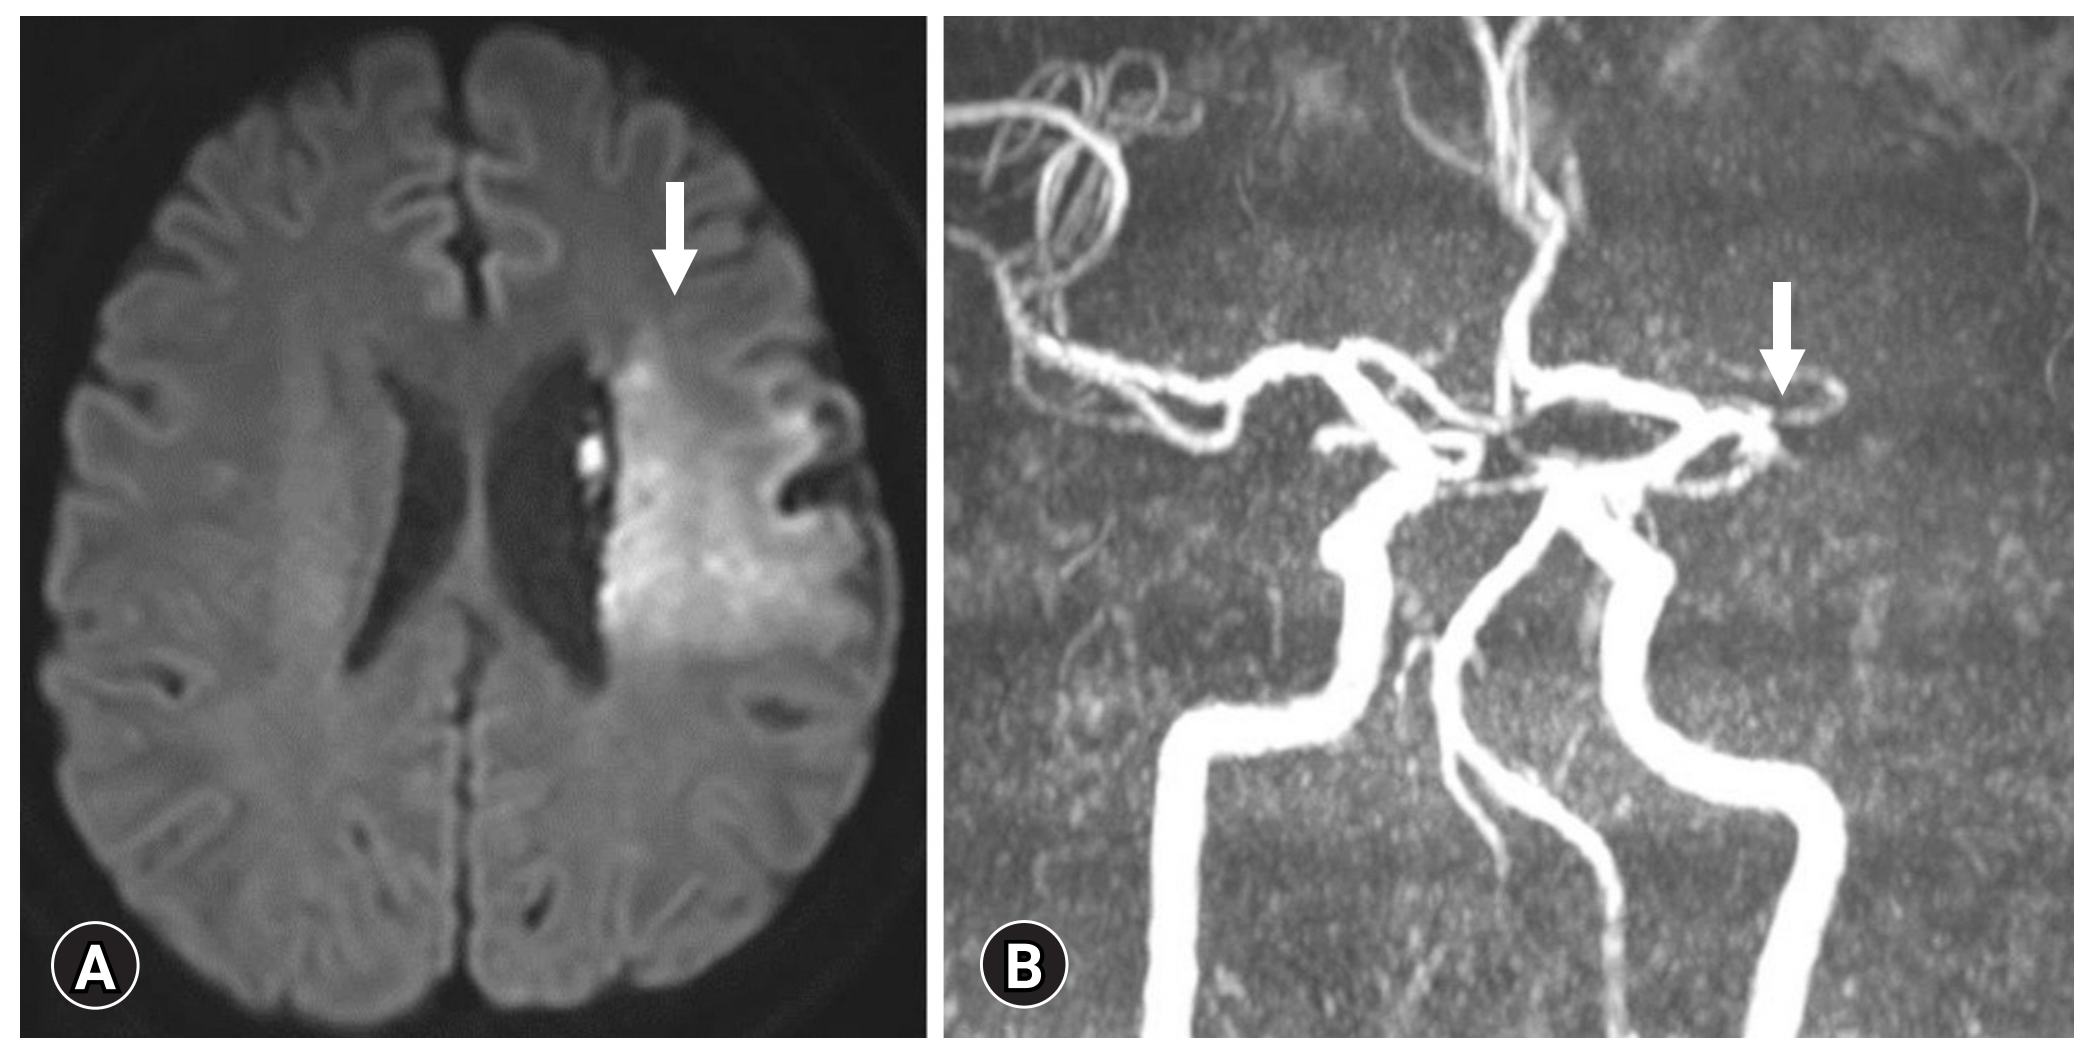

患者男,38岁,吸烟,有不明原因的心律失常史,无治疗,因右侧偏瘫入院。在初次检查时,患者处于昏迷状态,格拉斯哥昏迷评分为7分。患者被诊断为左大脑中动脉(MCA)区域梗死(图1A),左大脑中动脉M1段闭塞(图1B)。有房颤、心力衰竭伴左心室射血分数(LVEF) 27%(表1)、肺水肿、胸腔积液和轻度心脏扩大(图2)。

图1: (A)脑磁共振成像显示左侧大脑中动脉区域梗死(箭头)(弥散加权图像,轴位视图)。(B)脑磁共振血管造影显示左侧大脑中动脉M1段闭塞(箭头)